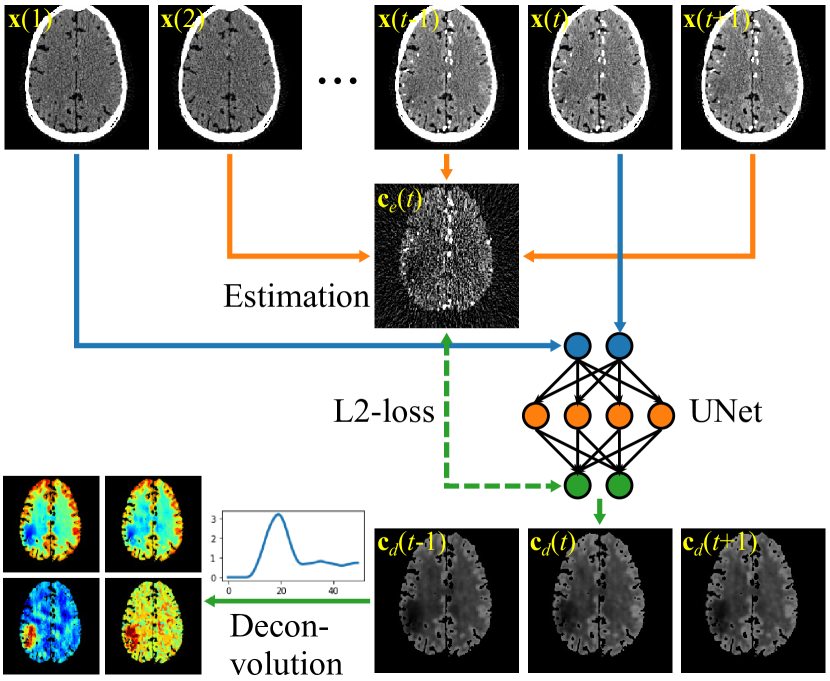

A diagram of the proposed Noise2Noise framework for CTP denoising is given in figure 1.

Refer to caption

Figure 1: Proposed Noise2Noise framework for CTP denoising. The blue lines demonstrate the inputs to the network. The orange lines demonstrate the estimation of 𝐜(t)𝐜𝑡\mathbf{c}(t). Averaging over early frames are not demonstrated for the simplicity of the figure.